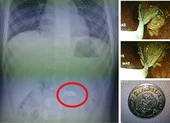

Tiến hành chụp phim, bác sĩ phát hiện một di vật nằm ở thực quản C6-C7. Sau đó, cháu V. được chuyển vào phòng mổ.

Cháu V. nuốt đồng xu vào bên trong thực quản. Ảnh: TT

Tại đây, các bác sĩ đã tiến hành nội soi và gắp thành công một đồng xu có đường kính 4 cm từ bên trong thực quản ra ngoài.